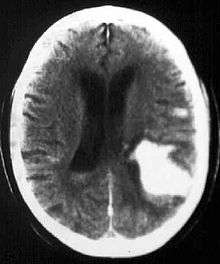

Intraparenchymal hemorrhage (IPH) is one form of intracerebral bleeding in which there is bleeding within brain parenchyma. The other form is intraventricular hemorrhage (IVH).

Intraparenchymal hemorrhage accounts for approx. 8-13% of all strokes and results from a wide spectrum of disorders. It is more likely to result in death or major disability than ischemic stroke or subarachnoid hemorrhage, and therefore constitutes an immediate medical emergency. Intracerebral hemorrhages and accompanying edema may disrupt or compress adjacent brain tissue, leading to neurological dysfunction. Substantial displacement of brain parenchyma may cause elevation of intracranial pressure (ICP) and potentially fatal herniation syndromes.

Computed tomography (CT scan): A CT scan may be normal if it is done soon after the onset of symptoms. A CT scan is the best test to look for bleeding in or around your brain. In some hospitals, a perfusion CT scan may be done to see where the blood is flowing and not flowing in your brain.